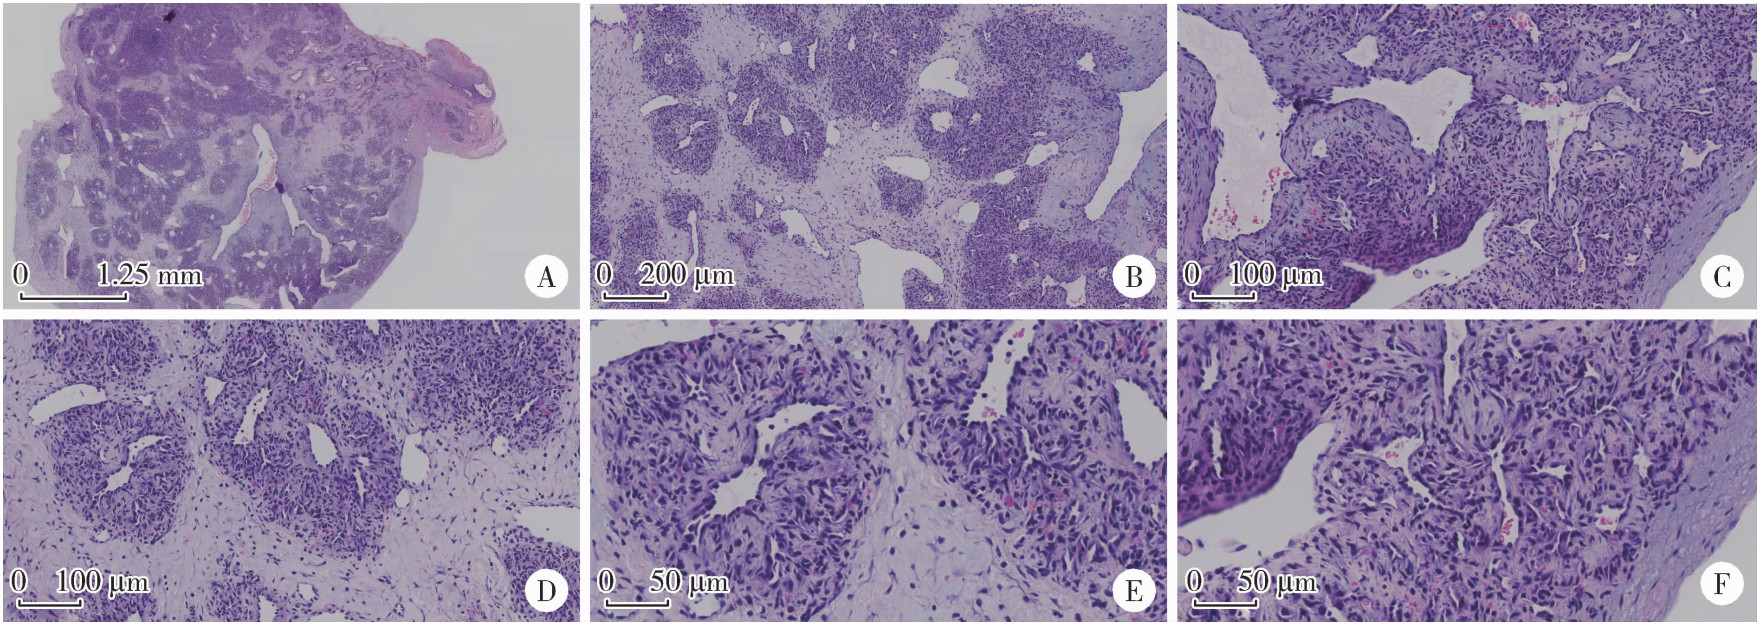

Figure 3

Pathological microscopic features of IPEH A, full view of intravascular tumor (20×); B, vascular endothelial hyperplasia, fibrous tissue hyperplasia, fibrous interstitial hyperplasia and recanalized vessels (40×); C, papillary structure (200×); D, endothelial lining fissures and papillary hyperplasia (200×); E, no obvious polymorphism of endothelial cells (400×); F, papillary structure (400×).IPEH, intravascular papillary endothelial hyperplasia."